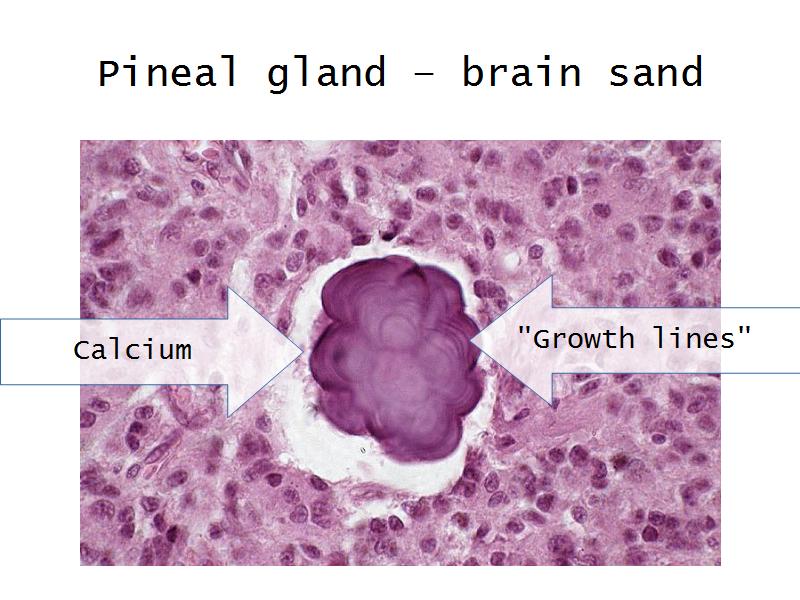

- Slide 34: Pineal gland

Pineal Gland